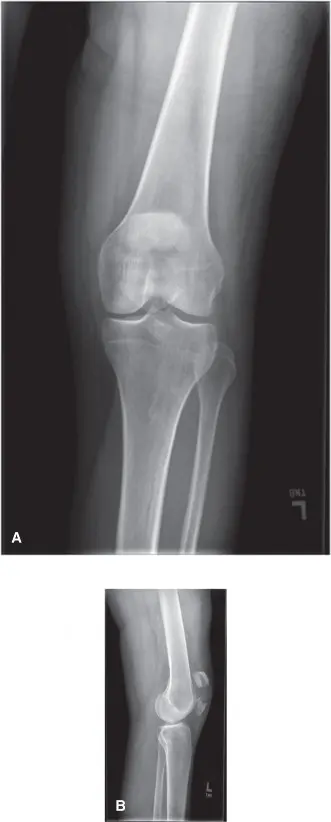

- تم الحصول على صور بالأشعة السينية للركبة اليسرى من الأمام والخلف (AP)، ومن الجانب (Lateral)، ومنظر شروق الشمس (Merchant view).

- منظر AP: أظهر كسرًا رضفيًا مفتتًا للغاية، مع خطوط كسر متعددة وفجوات كبيرة بين الشظايا.

- المنظر الجانبي (Lateral View): قدم معلومات حاسمة حول الإزاحة في المستوى السهمي وتأثر السطح المفصلي. أكد هذا المنظر التفتت الشديد والإزاحة الواضحة للشظايا. انسحبت الشظية العلوية بشكل ملحوظ إلى الأعلى بفعل سحب العضلة الرباعية، بينما بقيت الشظية السفلية ثابتة نسبيًا. لوحظ وجود "درجة" أو فجوة كبيرة، تشير إلى عدم تطابق شديد في السطح المفصلي الخلفي للرضفة.

الصورة التالية تمثل بشكل كبير المنظر الجانبي الذي تم الحصول عليه للسيد أحمد، وتظهر بوضوح التفتت الكبير وانسحاب القطب العلوي.

- منظر Merchant (Sunrise View): أظهر اضطرابًا كبيرًا في السطح المفصلي للرضفة داخل التلم البكري، مؤكدًا وجود شظايا متعددة داخل المفصل.